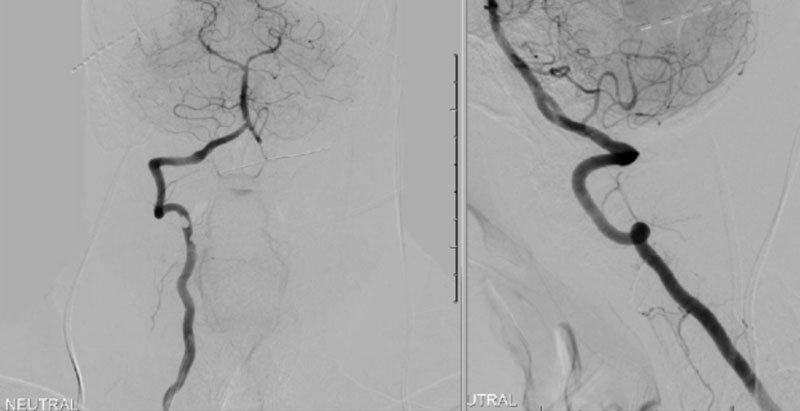

CTA of the neck and brain reveal that the left Vertebral Artery is completely occluded at approximately the C1-C2 level with extensive hypertrophic degenerative osseous changes from C1-C3. Retrograde flow into the post PICA left Vertebral Artery is observed from the co-dominant right Vertebral Artery which appears to be the primary supply into the basilar circulation. No significant Posterior Communicating arteries are observed on either the right or left Carotid Artery on the CTA imaging (Figure 1).

We performed conventional catheter angiography with provocative testing to reproduce his symptoms. The right Vertebral Artery is the codominant primary supply to the basilar circulation with reflux into the distal left Vertebral Artery that is occluded (Figure 3).

During neutral positioning, the vertebrobasilar circulation fills briskly from the Right Vertebral Artery. (Figure 4)